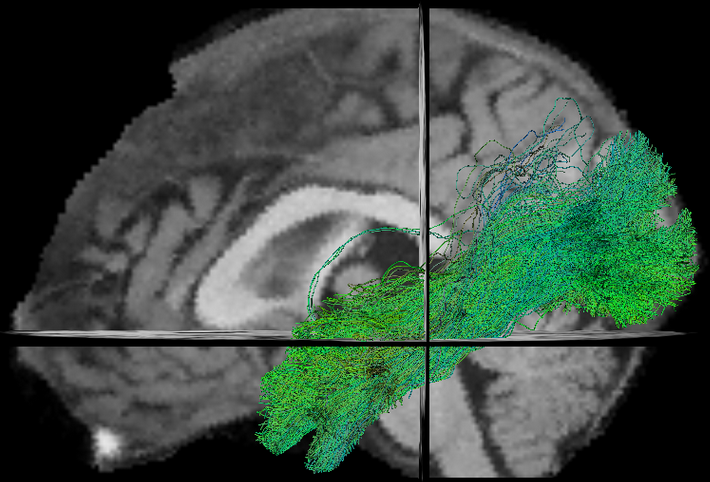

- TractFiltering (Cousineau et al 2016. ISMRM, Coté et al 2015. ISMRM)

- Tractometry (Cousineau et al 2016. ISMRM)

FA

NUFO

Metrics

- Mean value per bundle

- Mean value per point

- Profile

- Volume